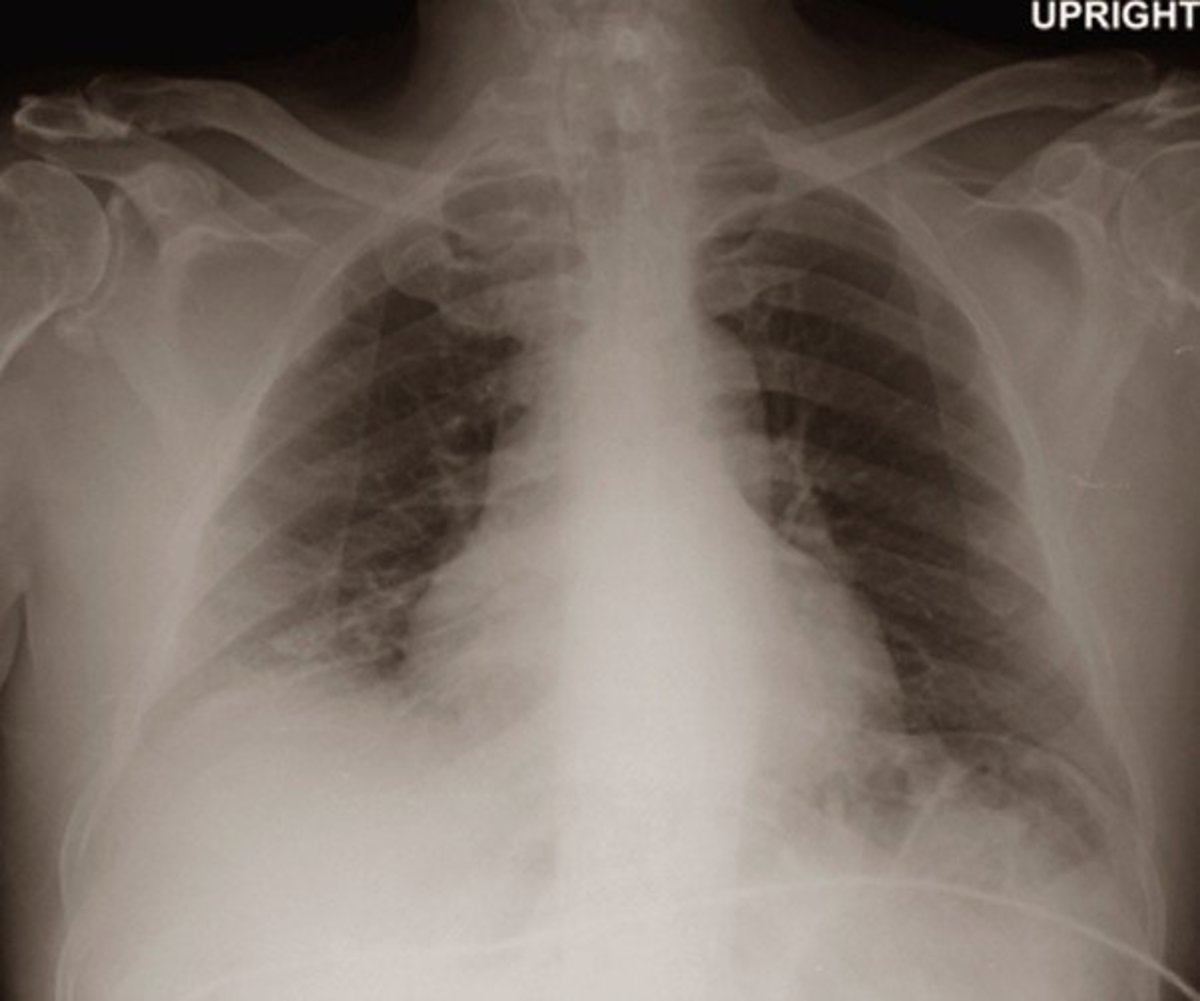

It excludes newborn atelectasis and. If it affects a greater portion, or the. Bibasilar atelectasis can be mild, affecting only a small portion of the lungs.

Atelectasis is condition where there is a complete or partial collapse of the lung field when the alveoli become deflated within the lung. It can fill with alveolar fluid or air can.